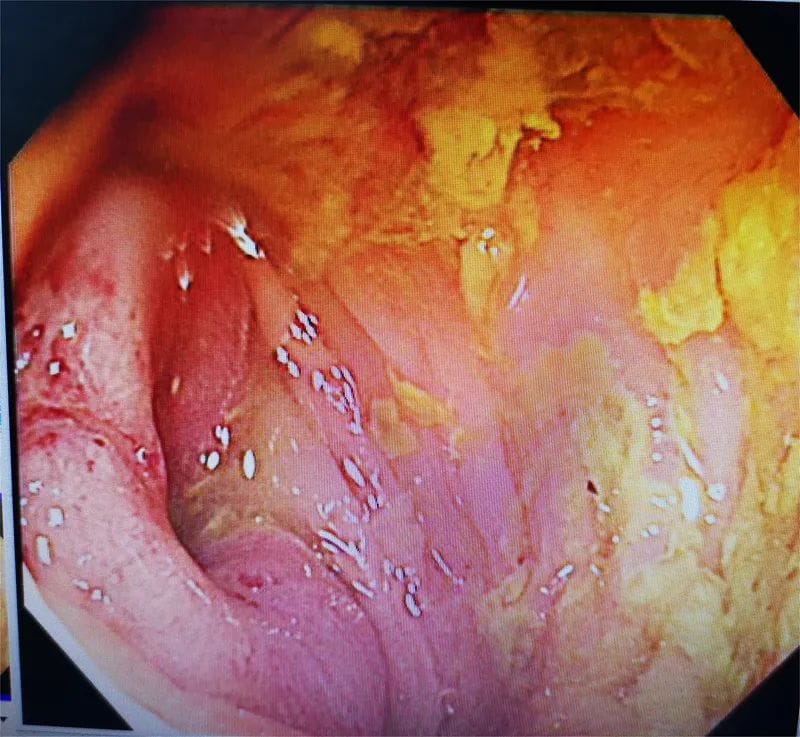

3月11日下午,邀请重庆医科大学第一附属医院文光旭教授作技术指导,在麻醉与围术期医学科和介入科的积极配合下,郭军博士带领团队利用C臂引导结肠造影为患者进行手术。医生在内镜下通过一根引导导丝将支架放到梗阻部位,并运用网状支架将肠道撑开,在堵塞的肠腔中撑开一条通道,形成真正意义上的“疏导”,为患者打通“生命通道”,手术顺利完成。

患者,老年男性,腹痛、腹胀、排便困难长达数月之久,近日因病情加重转诊至我院,来时患者呕吐隔夜宿食,腹胀如鼓,入院后,经各项检查初步诊断为横结肠肿瘤并胃、十二指肠及胆胰管、胰头及邻近腹膜组织、周围淋巴结转移,伴近端肠管梗阻扩张。消化内科主任医师郭军博士带领团队对病例进行评估,考虑到患者为恶性肿瘤晚期,全身状态欠佳,而置入肠道支架对患者来说创伤小、并发症少,病人痛苦小,恢复快,无疑是更优的选择。但该病患梗阻部位特殊,即横结肠近肝曲,该部位迂曲且薄弱,且肠道狭窄处仅约0.3-0.4mm大小,支架置入困难,有出血、穿孔、置入失败等风险。医生向患者及家属交代病情及风险后,家属果断选择内镜下结肠支架置入术。该手术是采用金属支架作为肠腔内支撑治疗结直肠恶性梗阻,对于患者来说就像做了一次胃肠镜检查。